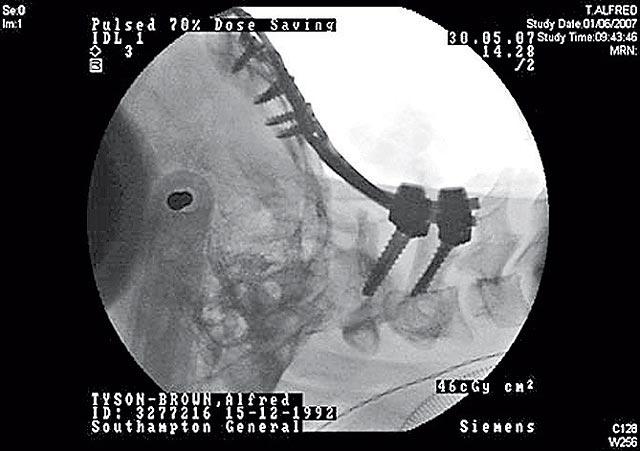

直至上月,他開始不時覺得頸痛和頭暈,某天踏單車時更無端失去平衡掉下地,心感不妥,乖乖看醫生。X光片一出,醫生和家人都大為吃驚,原來布朗一節頸椎骨早已斷裂,歪了的骨還壓着脊髓,手腳不聽話就是由此而起。他過去多年從無異樣,認真神奇。